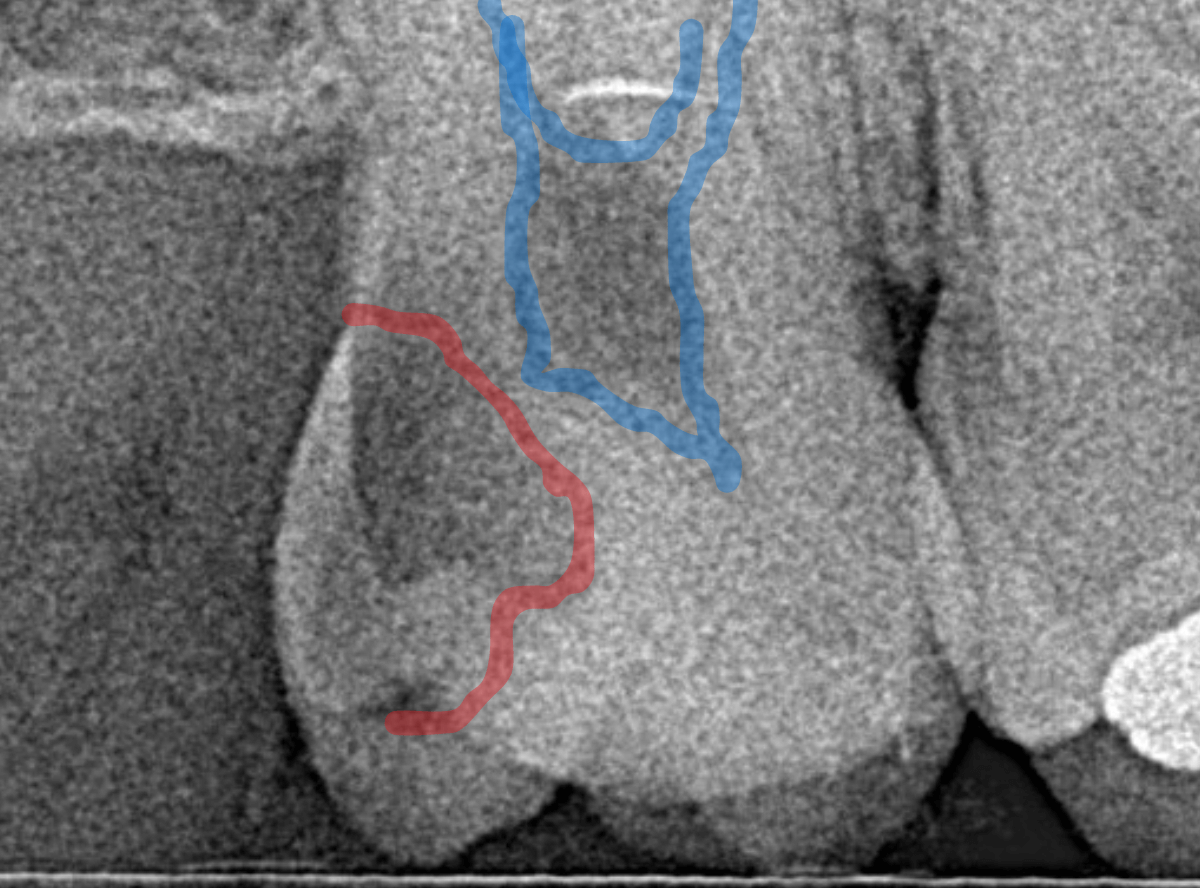

レントゲン写真で確認します。

青い線が歯の神経、赤い線が虫歯です。

おやしらずがあった際にはわかりづらかったですが、歯の後ろ側のおやしらずが重なっていたところが虫歯になっているのがわかります。

おやしらずが原因で、このように手前の歯が虫歯になってしまう事が多いために、抜歯を勧められる事が多いのです。

そして、虫歯の部分におやしらずが被さっていたために、しみる症状などを感じなかったのです。